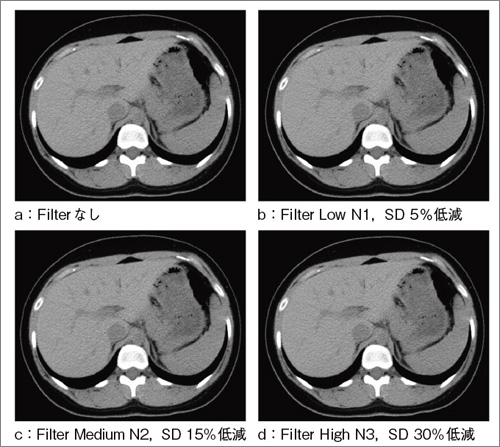

6.Neuro 3D Filter

Neuro 3D FilterはVCTに搭載されいるノイズ軽減フィルタであり,全身領域に使用可能である(図4)。MPRや3Dなどで使用する薄いスライスの場合,画像ノイズの増加が懸念されるが,Neuro 3D Filter使用により高画質を維持しながらノイズの低減が望める。

また,ルーチンワークに用いることで撮影時の線量を抑え,より低被ばくな撮影が実現できる。 |

| |

図4 Neuro 3D Filterの画像比較 |